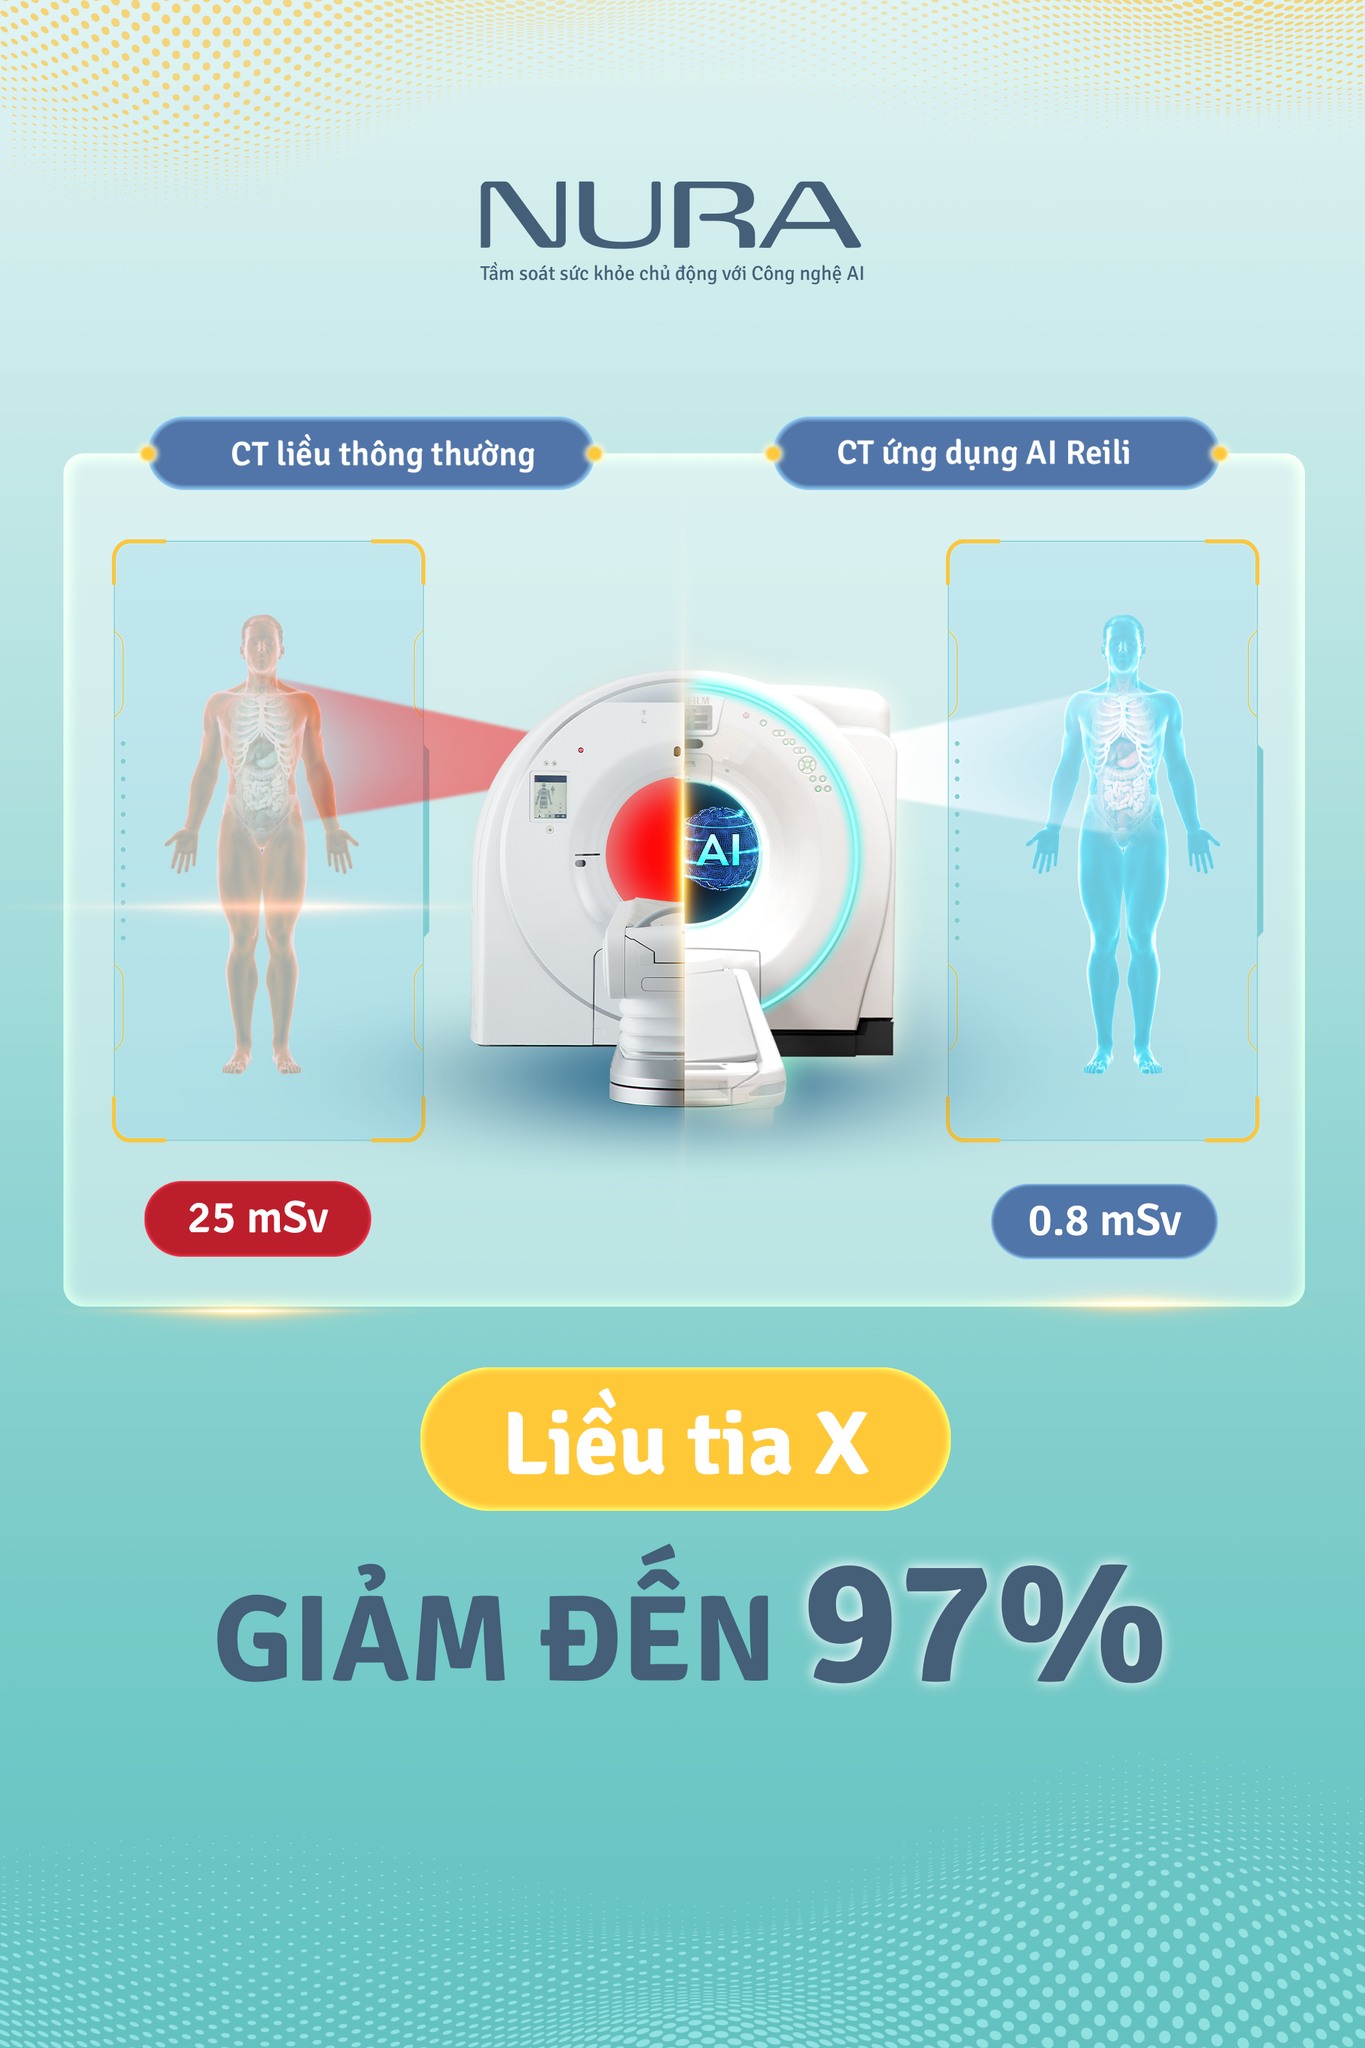

Máy chụp CT tại NURA được thiết kế để giúp quá trình tầm soát diễn ra thoải mái nhất có thể. Lỗ giàn máy của NURA (lỗ hổng mở trong máy CT – PV) lớn hơn các máy khác để giảm cảm giác sợ hãi và lo lắng của khách hàng. Đặc biệt, phòng chụp CT tại NURA được trang bị công nghệ tiên tiến nhất, đảm bảo không chỉ giúp chẩn đoán chính xác mà còn giảm thiểu tối đa bức xạ lên đến 97%, bảo vệ sức khỏe người bệnh. Bởi vậy, mọi người không cần phải tiêm thuốc cản quang trước khi chụp.

- Về tính an toàn: Công nghệ chụp CT tại NURA sử dụng liều tia cực thấp – giảm tới 97% so với mức thông thường. Nhờ đó, nguy cơ phơi nhiễm bức xạ được hạn chế tối đa, đảm bảo an toàn cho khách hàng, đặc biệt là những người cần tầm soát định kỳ.